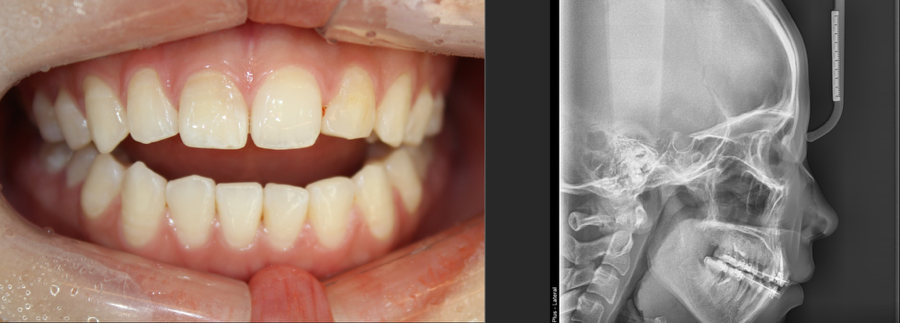

개방교합 비수술교정

안녕하세요 오늘은 개방교합 교정을 갖고왔습니다 해당 환자분또한 소개로 오셨는데 여러군데서 수술아니고는 어렵다는 소견으로 오셨습니다 저도 처음에는 완전히는 어렵지 않을까 조심스럽게 추측하면서 환자분을 분석해 보았습니다 환자분은다행히 최후방 구치만 먼저 닿아서 생긴 개방교합이라 협측 설측으로 각각 2개씩 미니스크류...

사잔 보시면 앞니가 열렸던부분이

닫히고

돌출해소까지 이루어졌습니다.

이분운 소구치 발치도 돌출로 4개 같이 진행했구요

일반적으로

돌출해소를 하면 바잇이 깊어지는것을

역으로 개방교합 해소에 이용했습니다.